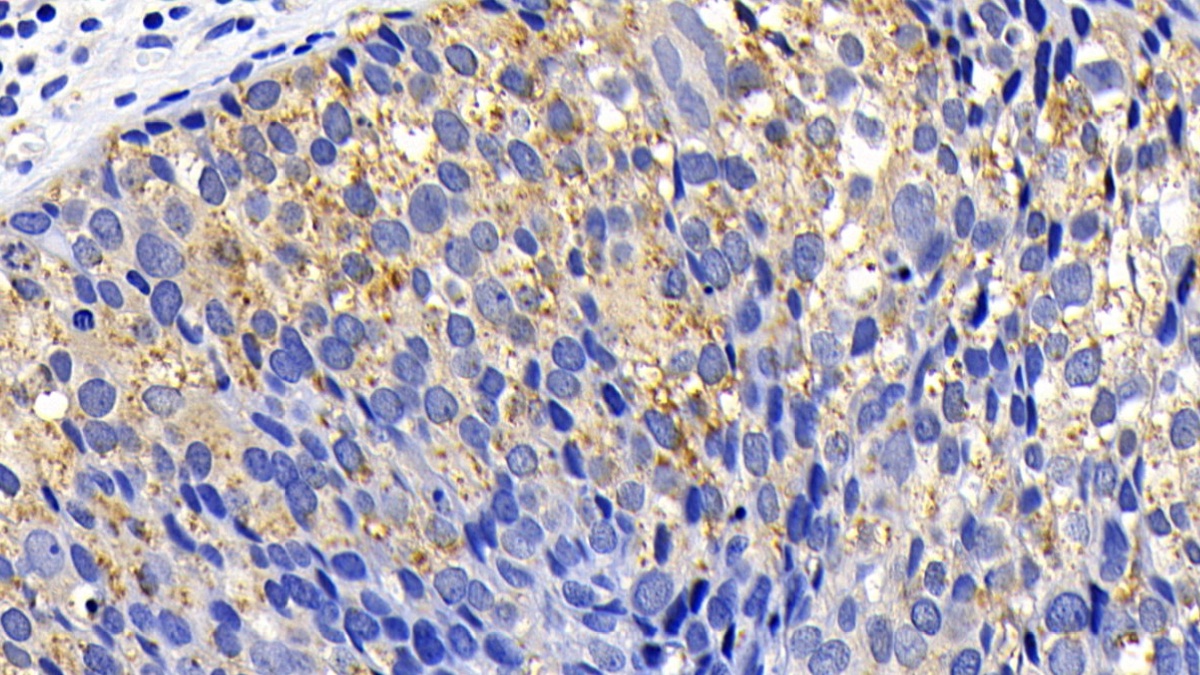

- ApplicationsIHC

The antibody is a rabbit polyclonal antibody raised against PUMA. It has been selected for its ability to recognize PUMA in immunohistochemical staining and western blotting.

Immunohistochemistry: 5-20µg/mL